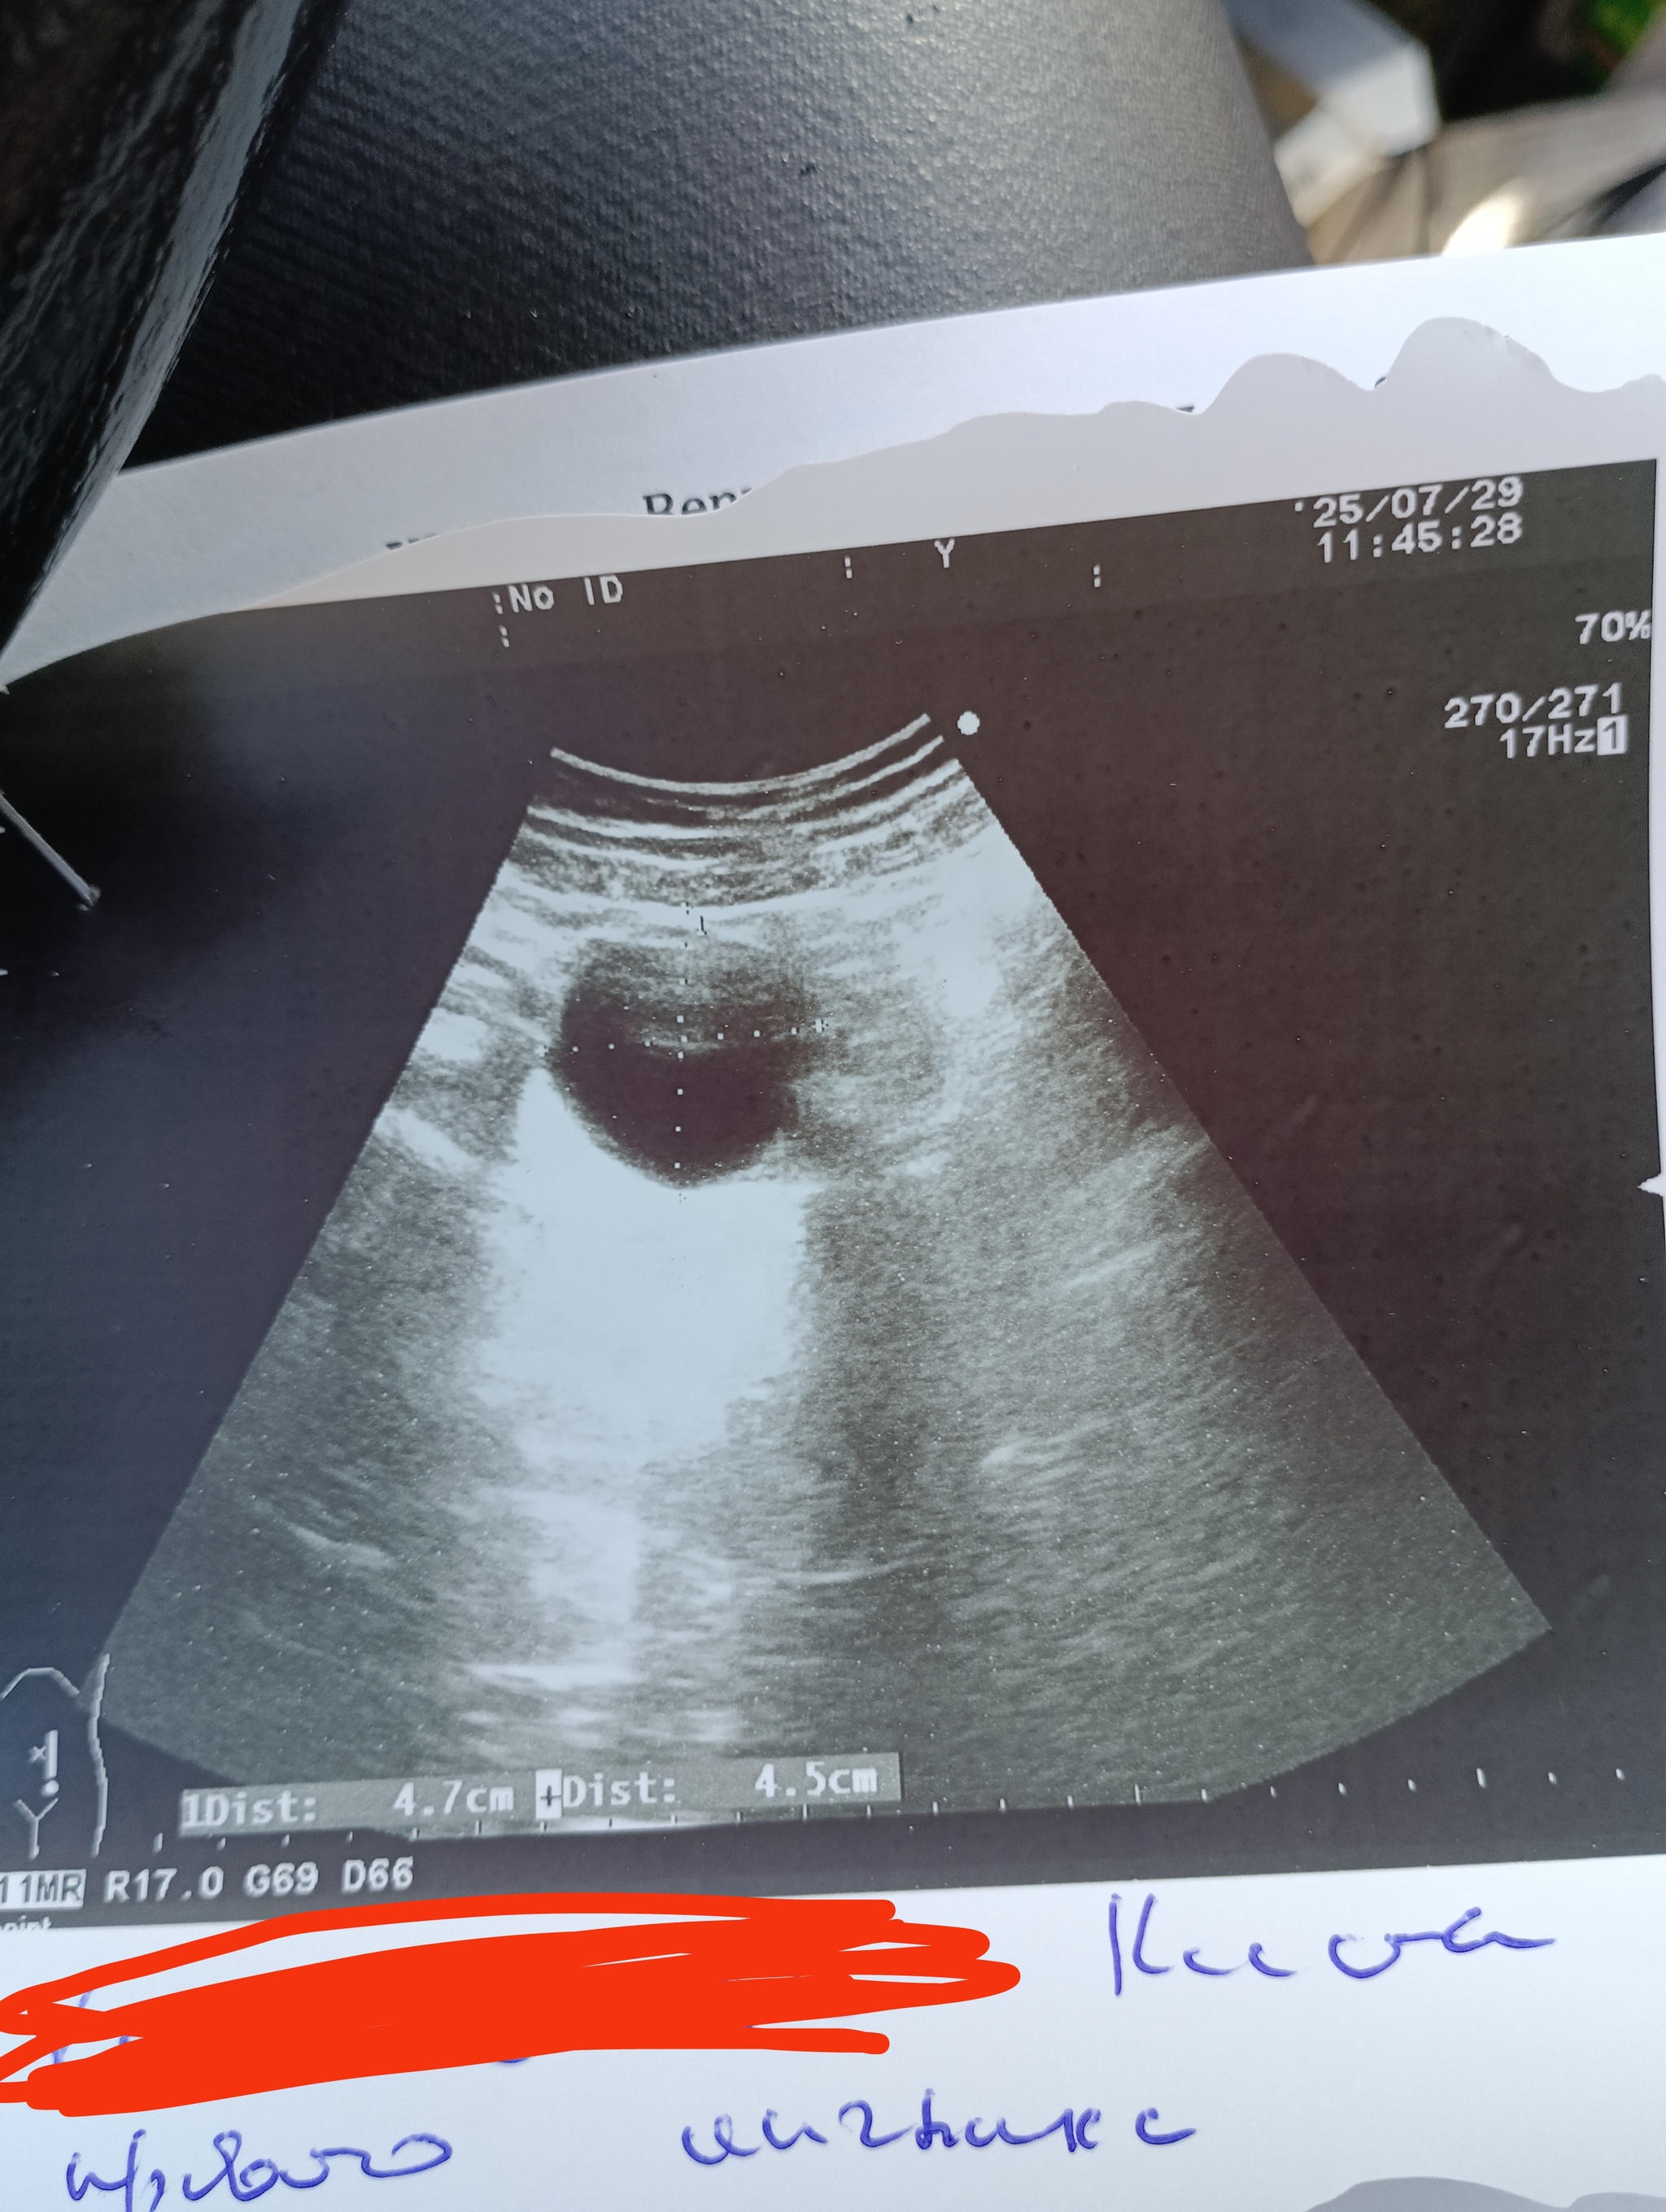

Добрый день. В последнее время у меня начало вызывать подозрения мое физическое здоровье. Постоянно повышенное давление (150 практически всегда),на учёте у кардиолога состою, таблетки пью,помогает,но не очень. Начались отеки, особенно с утра, и самое неприятное -постоянные позывы в туалет. Безболезненные,но просто очень хочется и очень часто-раз в час. Перетерпеть можно пару часов,но потом ноги вообще отекают . Вспомнила,что 2 года назад находили кисту в левой почке размером в 5 см.,сказали наблюдать в динамике,но у меня же ничего не болело,проблем не было и я забила. В связи с недавними обновлениями в моем организме сопоставила побочки от кисты и решила сходить на УЗИ. Все стало ещё туманнее-киста уменьшилась,но в туалет я по-прежнему бегаю как утка. Завтра пойду сдавать анализы,но хочется хоть не много понять ситуацию. Может Пикабу мне как-то развеет мой туман в голове? Узист сказал все норм по почкам,чеши к гинекологу (завтра на прием пойду).